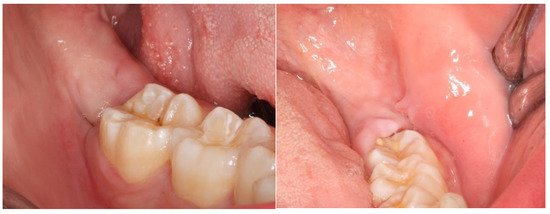

2. Materials and Methods

2.2. Definition of the Variables in Study and Follow-Up of Patients

3. Results